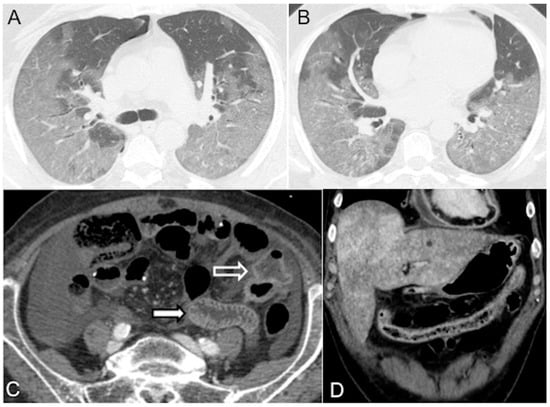

Figure 4.

CECT images in obstructive shock in a severely dyspneic 28-year-old man with malignant pulmonary artery sarcoma. Arterial (A) and delayed (B) phase axial images show massive pulmonary trunk (black arrow) and right main artery (white arrow) soft tissue mass obstruction. A more caudal (C) axial image shows CM stasis in right cardiac chambers, no hepatic enhancement, and mild pleuropericardial effusion. (D) Delayed phase (delay of 200 seconds after CM injection) coronal reconstruction shows a thinned flat IVC (black arrow).